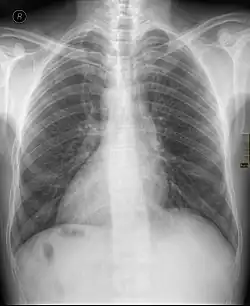

Dextrocardie

La dextrocardie est une malformation de naissance dans laquelle le cœur se trouve dans la moitié droite du thorax, l'hémithorax droit. La pointe du cœur est aussi orientée à droite.

L'anomalie peut être découverte lors d'un examen systématique, clinique ou radiologique, ou motivée par la présence d'autres malformations.